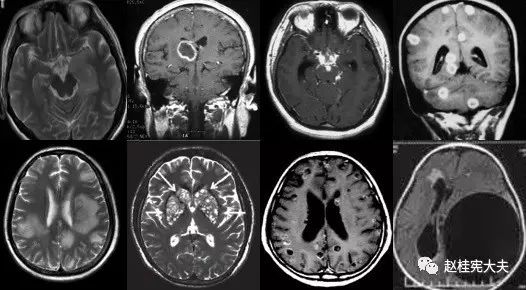

重要申明:以下每个部分会配磁共振图片,因疾病和影像之间存在同病异象、同像异病,为避免误导,图片不标注疾病,请各自鉴赏,另其中有部分图片来源于网络,有疑问可与本人联系。

N--neoplasm,肿瘤

各种肿瘤,如胶质瘤、淋巴瘤、脑膜瘤、血管内淋巴瘤,生殖细胞瘤、各种转移瘤、心房粘液瘤等。神经纤维瘤病也可在中枢出现影像学上类似脱髓鞘的病变。

I--infection,感染

指的是各种感染,病毒(单纯疱疹病毒、带状疱疹…)、细菌(革兰阳性、革兰阴性、球菌、杆菌…)、结核、。真菌、梅毒、各种寄生虫(囊虫、弓形虫、吸虫、裂头蚴等)。还有进行性多灶性白质脑病(PML)、CJD、Whipple’s 病等。亚急性细菌性心内膜炎。